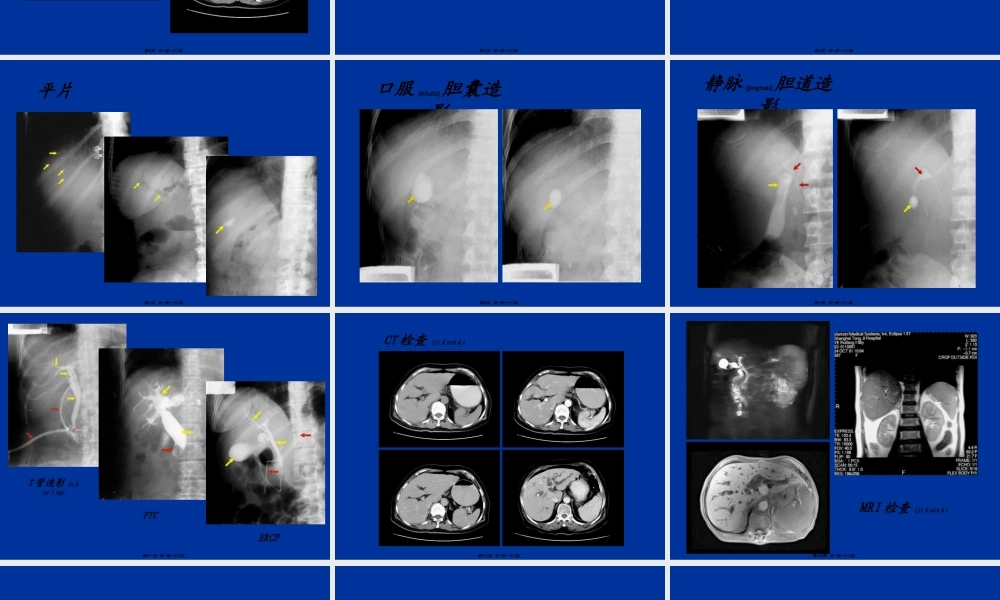

消化系统(xiāohuàxìtǒng)影像学第一页,共一百一十二页。普通检查腹部平片价值有限(yǒuxiàn)透视少用第二页,共一百一十二页。钡剂造影检查范围:上消化道全消化道结肠方法:1、常规法(粘膜相、充盈相、加压相)2、气钡双重造影显示细微结构3、小肠灌钡造影4、结肠造影(灌肠(guàn〃cháng)法、口服法)血管造影胃肠道出血CT第三页,共一百一十二页。造影(zàoyǐng)检查钡餐(bèicān)造影小肠(xiǎocháng)造影钡剂灌肠造影第四页,共一百一十二页。胃肠道CT检查(jiǎnchá)第五页,共一百一十二页。平片:显示阳性结石术后经T形管造影内镜逆行(nìxíng)性胰胆管造影(Endoscopicretrogradecholangio-pancreatography,ERCP)经皮肝穿胆管造影(Percutaneoustranshepaticcholangiography,PTC)CTMRI,MRCP第六页,共一百一十二页。X线检查价值有限CT:平扫增强(zēngqiáng):动脉期、门脉期;实质期MRI:平扫、增强、动态增强MRA第七页,共一百一十二页。平片第八页,共一百一十二页。口服(kǒufú)胆囊造影第九页,共一百一十二页。静脉(jìngmài)胆道造影第十页,共一百一十二页。ERCPPTCT管造影(zàoyǐng)第十一页,共一百一十二页。CT检查(jiǎnchá)第十二页,共一百一十二页。MRI检查(jiǎnchá)第十三页,共一百一十二页。第十四页,共一百一十二页。咽:会厌(huìyàn)梨状窝第十五页,共一百一十二页。轮廓光整管状影数条平行走行的粘膜皱襞四个狭窄食道入口处狭窄;主动脉弓压迹;左主支气管;横膈裂孔部狭窄膈壶腹胃食管前庭(qiántíng)蠕动波第十六页,共一百一十二页。食管(shíguǎn)第十七页,共一百一十二页。X线分区形态轮廓(lúnkuò)粘膜皱襞微皱襞胃小区胃小沟蠕动波第十八页,共一百一十二页。胃底胃角胃体胃小弯胃大弯第十九页,共一百一十二页。鱼钩(yúɡōu)型牛角(niújiǎo)型瀑布(pùbù)型无力型第二十页,共一百一十二页。胃粘膜、胃小区(xiǎoqū)、胃小沟第二十一页,共一百一十二页。十二指肠:"C"形球部框部空肠与回肠:分组结肠(jiécháng):结肠(jiécháng)袋无名沟无名区第二十二页,共一百一十二页。第二十三页,共一百一十二页。第二十四页,共一百一十二页。第二十五页,共一百一十二页。轮廓改变crater憩室充盈缺损(fillingdefect)粘膜改变破坏(pòhuài)平坦增宽纡曲纠集微粘膜皱襞改变管腔大小异常位置及可动性异常...